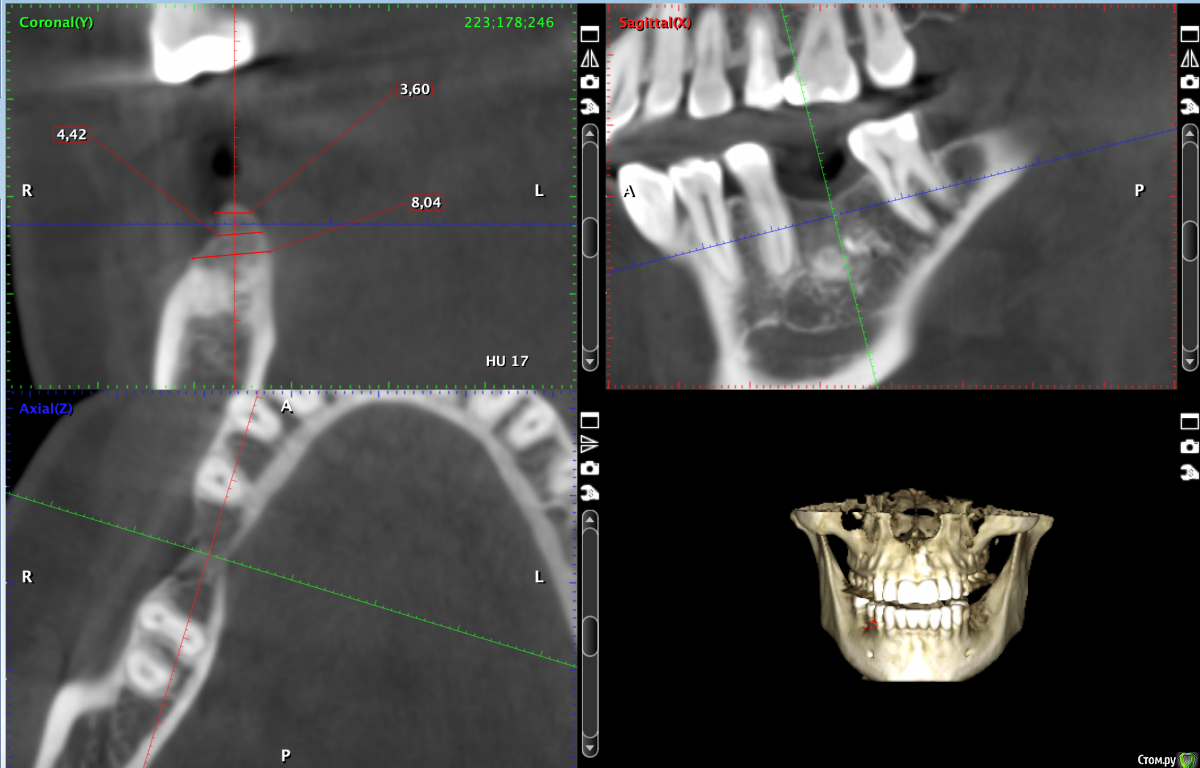

Valerkaa Опубликовано 14 декабря, 2019 Поделиться Опубликовано 14 декабря, 2019 (изменено) Уважаемые доктора, помогите, пожалуйста, советом. Опыт в имплантации небольшой, хотелось бы принять правильное решение.Планируется имплантация в области отсутсвующего 4.6. Помимо остатков выведенного материала (думаю, уйдет при формировании ложа), есть недостаток по ширине. Подумываю над имплантацией+одномоментно кость+мембрана. Или лучше разбить в 2 этапа и сделать "сосиску"? Также подумывала над резекцией гребня по высоте, но думаю, слишком уж большой вертикальный дефект получится (около 4мм). Изменено 14 декабря, 2019 пользователем Valerkaa Ссылка на комментарий

Valerkaa Опубликовано 15 декабря, 2019 Автор Поделиться Опубликовано 15 декабря, 2019 Большое спасибо. Вот с размерами. №1 и №2 Ссылка на комментарий